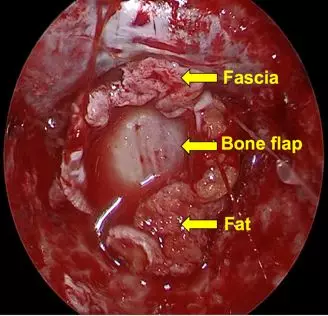

• The defective area was sealed with artificial dura sutured to the remaining dura

• Sellar floor reconstruction was performed using layers of fat, fascia, and nasal turbinate tissues